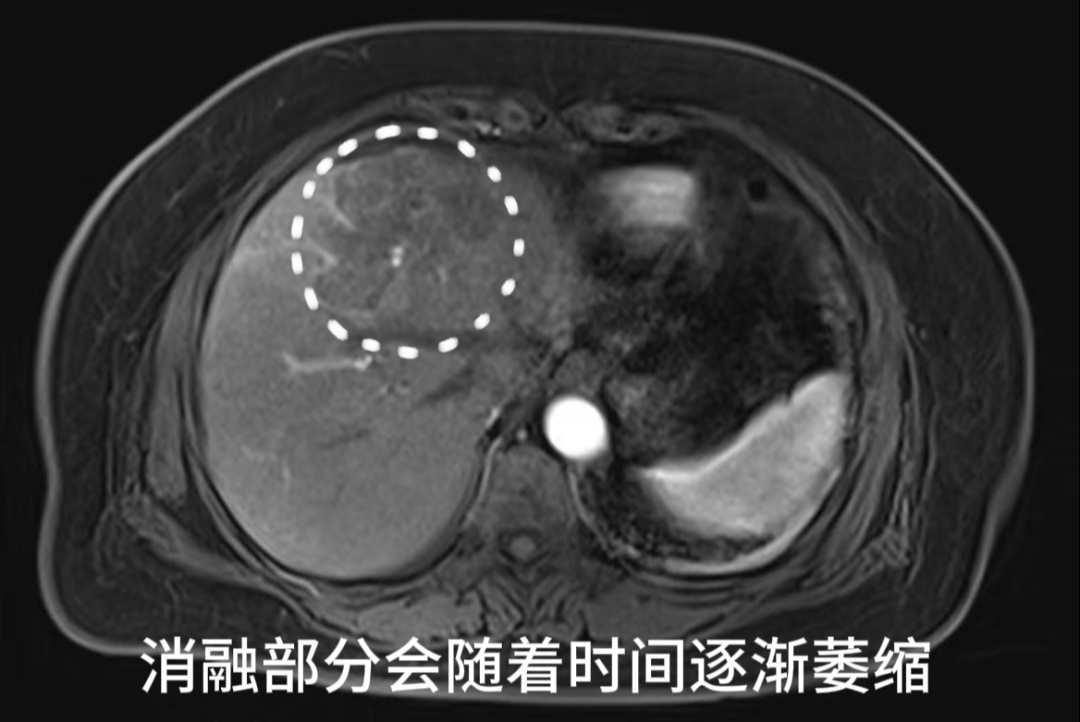

患者术后第二天MR

复查结果提示未见肝内有强化病灶,肿瘤完全失去了活性。经外周静脉注射造影剂Sonazoid后,病灶区域始终未灌注区,显示消融效果满意。